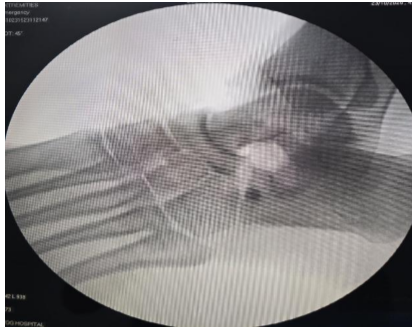

After thorough irrigation, the wound was closed in layers: Deep fascia and retinaculum were approximated, subcutaneous tissue closed with absorbable sutures, and skin with interrupted non-absorbable sutures. A below-knee posterior slab was applied in neutral ankle position for 2 weeks. The post-operative course was uneventful. The patient was started on toe-touch walking the next day, immediately followed by gradual ankle mobilization and physiotherapy [4]. By 3 weeks, she achieved a full, pain-free range of motion, and by 12 weeks, she returned to sports training. There was no recurrence at 6-month and 1-year follow-ups (Fig. 9).

Figure 9: 12 months follow-up X-ray of the foot showing maintained space between calcaneum and naviculum.